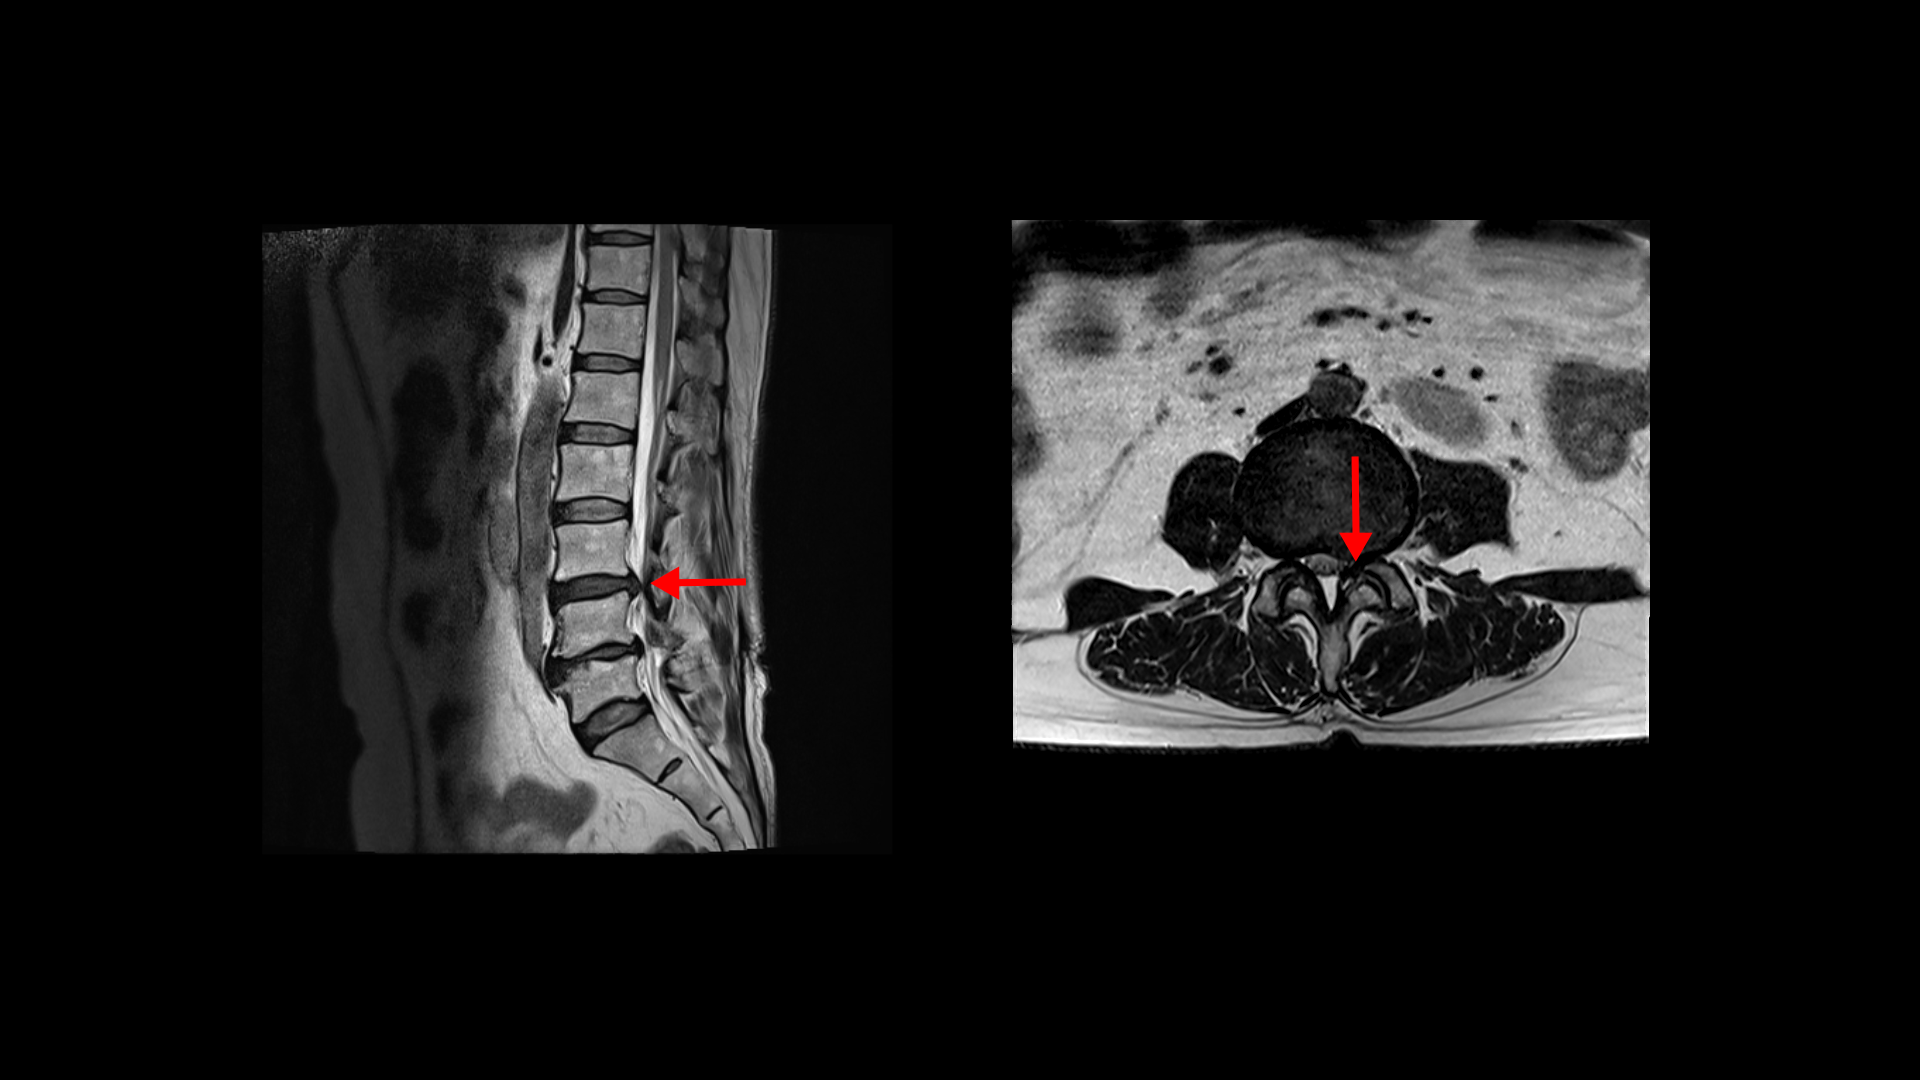

허리MRI를 보면 두 마디의 퇴행성디스크와 추간공협착이 있습니다.

3번 4번은 왼쪽 중앙으로 밀려나와있고

4번 5번은 왼쪽 신경이 빠져나가는 추간공이 뼈가 자라면서 좁아져 추간공협착이 있습니다.

또 왼쪽 후궁에는 과거에 받은 수술의 흔적도 보입니다.